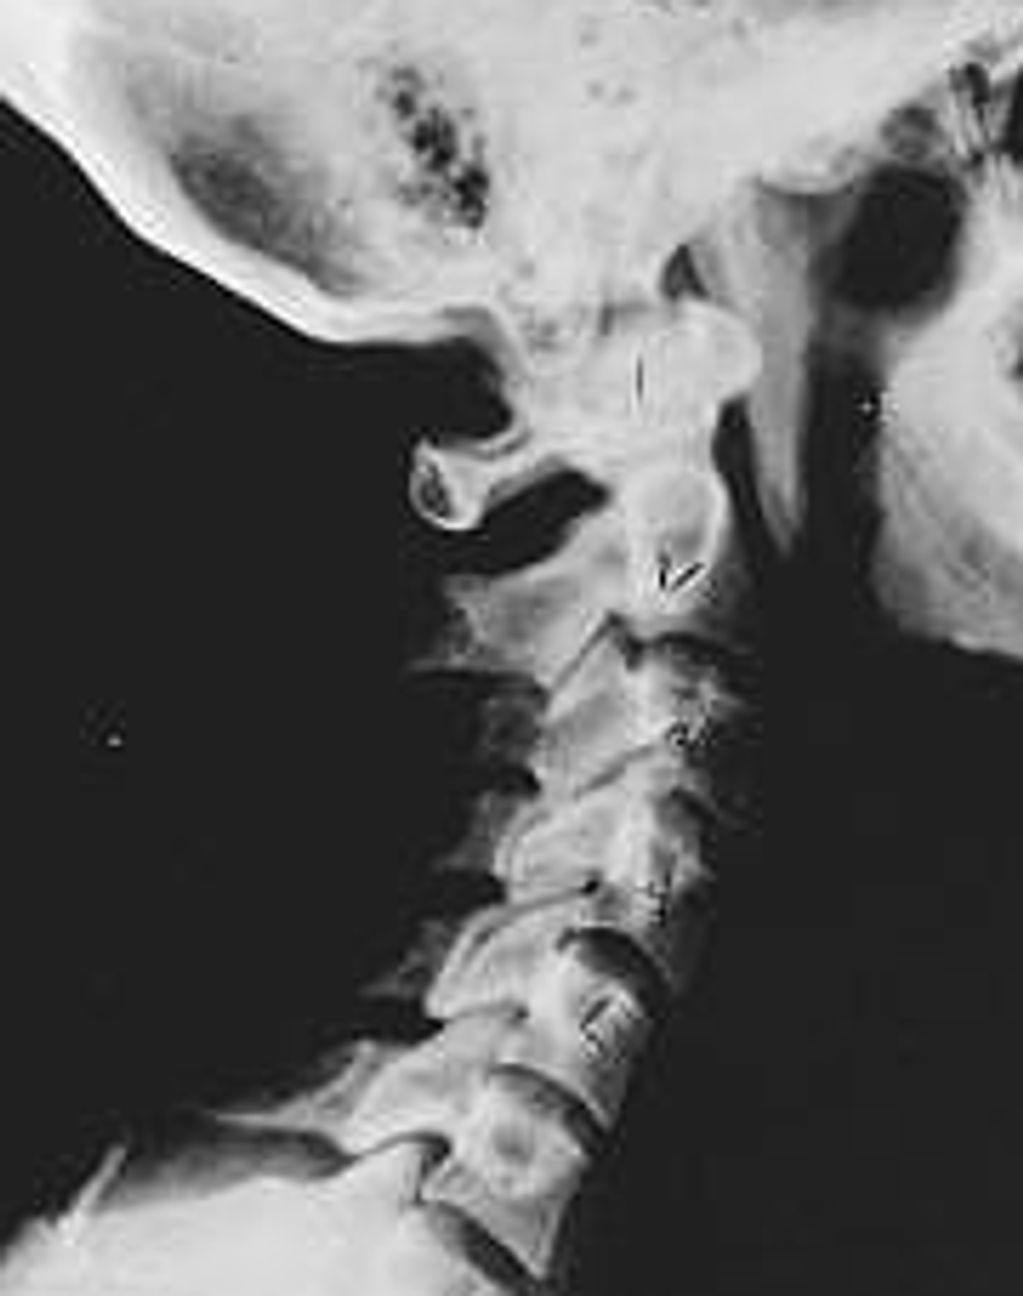

Phase Three Subluxation Degeneration

Phase Three Subluxation Degeneration is caused by subluxations that have been continuing on for between 40 and 65 years. This phase has all of the attributes of the previous phases, only worse. The curvatures are abnormal, the disc spaces are vastly decreased and changed. Calcium changes on the spine are abundant in this phase. Normally, people in phase th